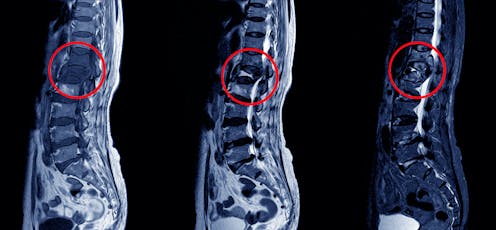

Investigations include X-rays, CT scans or MRIs and sending appropriate specimens to the laboratory to detect the TB bacterium. The type of specimen that should be sent depends on the organ system involved. For example, in the case of lymph node TB, a biopsy (tissue specimen) of the lymph node should be sent to the laboratory; in the case of pleural TB, pleural fluid should be sent for testing.